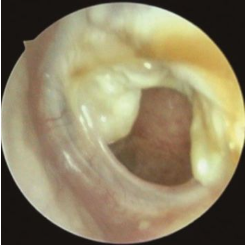

急性中耳炎:好比是中耳这个房间的“急性感冒”,来得快,去得也快,通常鼓膜能完好愈合。

中耳炎鼓膜穿孔

慢性化脓性中耳炎:就是这次“感冒”后,留下了后遗症——鼓膜破了个洞,一直长不好。这个穿孔就像一扇关不紧的门,让细菌和病毒可以随时进出,导致感染反复发作,持续流脓。通常流脓、穿孔的过程会持续超过3个月。